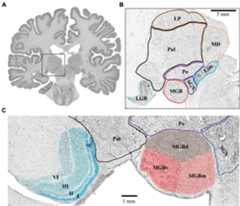

The MGB and LGB followed a consistent topography in all analyzed postmortem brains. The LGB was located ventrolaterally of the pulvinar of the thalamus. It showed the typical 6-layered pattern with sharp bends. The MGB was always located medially to the LGB. Its caudal pole protruded from the caudal extremity of the diencephalon. The caudal pole itself was located caudoventrally of the posterior nuclear complex (i.e., the compact limitans, suprageniculate and posterior nucleus of the thalamus) and medially of the inferior pulvinar nucleus of the thalamus (Figure 1). The caudal surface of the pretectum formed the dorsomedial flank of the MGB.

Figure 1. Topography of the MGB and LGB.(A) Cell-body stained section (number 3660, caudal MGB) from the left hemisphere of postmortem brain pm 21. The dashed box indicates the location of the thalamus magnified in panel(B).(B) Magnified crop from panel(A) showing the topography of the MGB and LGB (cyan and red) in comparison to putative locations of other thalamic nuclei.(C) Magnified crop from panel(B) depicting the layered structure of the LGB (cyan, left side) and the subdivisions of the MGB (red, right side). Roman numerals indicate layers of the LGB; LGB, lateral geniculate body; MGB, medial geniculate body; MGBv, ventral subdivision of the MGB; MGBd, dorsal subdivision; MGBm, medial subdivision; Po, posterior nucleus; SGN, suprageniculate nucleus; Lim, compact limitans nucleus; Pul, pulvinar; MD, mediodorsal nucleus; LP, lateral posterior nucleus.